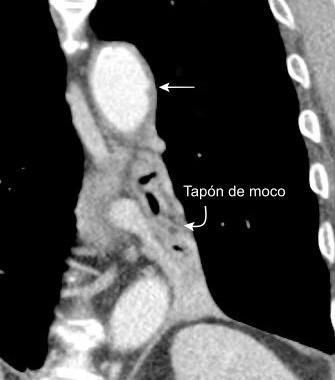

30 años

Borramiento de la banda PARA-aórtica por AdenoCa. de LII, no visible en 2005

Colapso de LII. TC: secreciones bronquiales.

Endoscopia tapón mucopurulento extraído

Borramiento parcial por Ca. epidermoide.